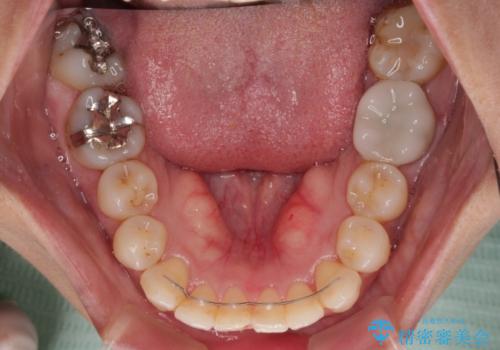

【モニター】処置歯の多い歯列 インビザラインでデコボコを整える

術中や仕上がりに特に大きなトラブルはなく、スムーズに治療を終えることができました。

- 上下前歯のデコボコを気にして来院された患者様です。

歯列としては、ワイヤー装置でもインビザラインでも、どちらでも対応可能でしたが、処置されている歯が多く、ワイヤー装置を装着するためには処置歯のやり直しが必要な状態でした。

インビザラインでもアタッチメントを装着できないという同様のデメリットがありますが、比較的矯正治療を行いやすい歯列であったので、インビザラインによる矯正治療を行うこととしました。